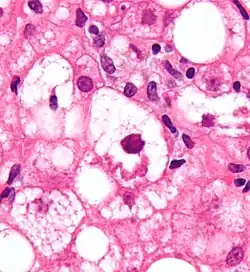

Mallory-Körperchen in einer ballonierten Leberzelle (Bildmitte), HE-Färbung.

Bei sogenannten Mallory-Körpern handelt es sich um Einschlusskörper in Zellen der Leber, die erstmals von dem amerikanischen Pathologen Frank Burr Mallory (1862–1941) beschrieben wurden.[1] Um den späteren Beitrag des Grazer Pathologen Helmut Denk zu deren weiteren Erforschung zu würdigen, ist auch die Bezeichnung Mallory-Denk-Körper vorgeschlagen worden.[2]

Mallory-Körper treten insbesondere bei der Alkohol-toxischen Hepatitis auf, kommen aber auch bei anderen Erkrankungen der Leber wie zum Beispiel der primären biliären Zirrhose oder dem Morbus Wilson vor. Die an der Bildung beteiligten Mechanismen sind komplex und beinhalten unter anderem eine Proteinfehlfaltung, Veränderungen von Chaperon-Proteinen und eine unverhältnismäßige Expression von Zytokeratinen.[3]